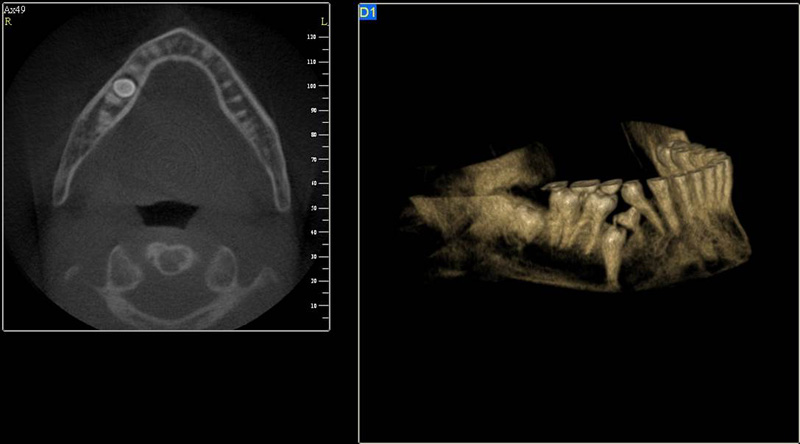

3D DVT - NewTom

Je speciální zubní digitální tříprostorový tomograf (3D), který umožňuje na základě jediného

snímkování vytvořit všechny typy RTG zobrazení, které jsou pro lékaře potřebné. Díky používané technologii tzv. „kuželového paprsku“ a speciálním senzorům je

výrazně zmenšená dávka záření - o více jak 80% proti klasickému CT vyšetření. To je významné zejména u dětí. Pomocí tohoto přístroje je možné zjisti skutečnou situaci v čelistních kostech pacienta tedy množství kosti - můžeme změřit skutečnou šířku i výšku kosti, i kvalitu kosti (hustotu) v místě uvažované implantace. 3D (tříprostorové) zobrazení umožňuje zvýšit prostorovou představu operatéra ještě před vlastní operací a zároveň pacientovi lépe objasnit a ukázat oblast plánovaného zavedení implantátu.

Pacient „neumí číst“ RTG snímky, ale díky 3D zobrazení vidí „svoji skutečnou čelist“

- např. jak je nízká či úzká, vidí průběh nervu nebo velikost čelistní dutiny, což mu umožní i pochopení nutnosti v některých případech provést pomocné zákroky ještě před vlastním zavedením implantátu (viz. kostní štěp, sinus lift, kostní granulát...).

Vyšetření pomocí tohoto přístroje používáme i ve stomatochirurgii (zlomeniny čelistí, zuby moudrosti, cysty, onemocnění čelistního kloubu), ortodoncii (retinované zuby, nadpočetné zuby), parodontologii atd.